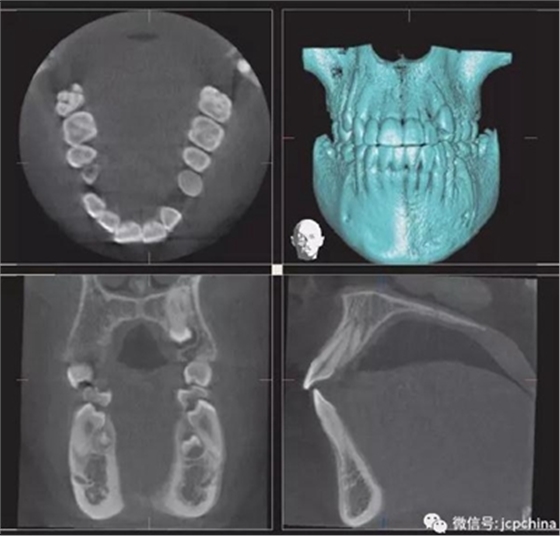

(2)射線硬化偽影

當(dāng)投射線的低能量光子被大量過(guò)濾時(shí)(如口腔銀汞),使透射過(guò)的剩余光子平均能量非常高,當(dāng)反投射時(shí),就會(huì)出現(xiàn)條狀偽影。由于口腔修復(fù)材料的阻射性質(zhì),因而射線硬化偽影非常常見(jiàn)。

(a)根尖片。

(b)CBCT矢狀面。

同一解剖位置顯示出的廣泛射線硬化偽影,使CBCT分辨金屬邊緣變得困難。CBCT圖像中27牙的近中壁缺損可能為齲損(紅色箭頭),而根尖片(黃色箭頭)卻顯示正常。